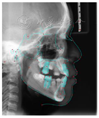

头颅侧位片示:下颌相对颅底位置靠前,趋向Ⅲ类错

,上下切牙舌腭向倾斜,骨龄CS1起始期。

患者治疗前头影测量分析结果

| 北京大学分析法 | ||||

|---|---|---|---|---|

| 测量结果 | 测量值 | 正常值 | 标准差 | 诊断提示 |

| 骨测量 | ||||

| SNA | 84.5° | 82.3 | 3.5 | 上颌相对颅底位置正常 |

| SNB | 81.9° | 77.6 | 2.9 | 下颌相对颅底位置靠前 |

| ANB | 2.6° | 4.7 | 1.4 | 趋向Ⅲ类错![]() |

| FH-NPo | 87.4° | 83.1 | 3 | 颏部前突 |

| NA-Apo | 2.9° | 10.3 | 3.2 | 上颌相对面部后缩 |

| FMA | 28.1° | 31.8 | 4.4 | 均角型 |

| SGn-FH | 62.1° | 65.5 | 2.9 | 聚合生长型,颏部前突 |

| MP-SN- | 32.5° | 35.8 | 3.6 | 下颌提陡度、面部高度适宜 |

| Po-NB | 2mm | 0.2 | 1.3 | 颏部发育量较大,颏部前突 |

| 牙测量 | ||||

| U1-NA | -1.2mm | 3.1 | 1.6 | 上中切牙后缩 |

| U1-NA | 7° | 22.4 | 5.2 | 上中切牙腭向倾斜 |

| L1-NB | 3.5mm | 6 | 1.5 | 下中切牙后缩 |

| L1-NB | 19.4° | 32.7 | 5 | 下中切牙舌向倾斜 |

| U1-L1 | 151.1° | 122 | 6 | 上下前部牙弓突度较小 |

| U1-SN | 91.5° | 104.8 | 5.3 | 下中切牙相对前颅底平面舌向倾斜 |

| IMPA | 85.1° | 94.7 | 5.2 | 下中切牙相对下颌平面舌向倾斜 |